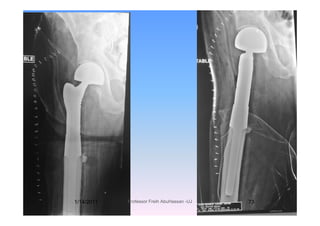

Neck femur

If destruction is limited to the

f l k h dfemoral neck or head

C t d H i th l t= Cemented Hemi arthroplasty

= Cemented Total Hip replacementCemented Total Hip replacement.

Long Stem Cementedg

Hemiarthroplasty

i fTrochanteric fractures

May require cemented arthroplastyMay require cemented arthroplasty

if there is significant destruction ofif there is significant destruction of

bone.